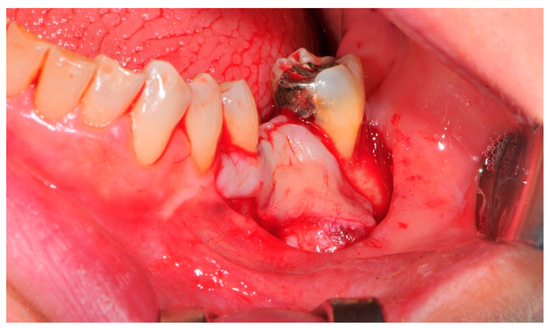

- Flap design: Soft tissue management should be as accurate as possible. The design of the flap should ensure a tension-free primary closure of the wound even after voluminous grafting of the defect. One option (preferred especially in wide vertical defects) is the execution of the so-called “poncho” flap. This technique includes a high vestibular incision of the mucosa, muscle and periosteum in order to undermine the preparation of the flap and to achieve its mobilization, followed by a deep incision in the buccal area with two additional vertical incisions that are performed at an appropriate distance from the occlusal area and the site of augmentation. After the incision, the preparation of a muco-periosteal flap and the remotion of scar tissue, a full thickness flap is raised until the bone defect is uncovered [17,18,19,20]. Finally, the positioning of the customized titanium mesh is passively tested to evaluate its fit intra-operatively (Figure 2, Figure 3, Figure 4 and Figure 5).